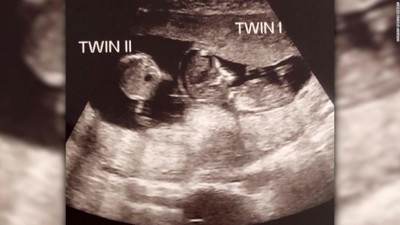

Hamileyken hamile kaldı. Hamileliğin üçüncü ayında öğrendiler Britanya’da, 39 yaşındaki Rebecca Roberts ve 43 yaşındaki baba Rhys Weaver’ın farklı zamanlarda aynı anda doğan iki çocuğu oldu. Roberts, ilk çocuğuna hamile kaldıktan 3 ay sonra ikinci çocuğuna da hamile kaldığını öğrendi. Çift, bu durumu ‘çılgınca’ olarak değerlendirdi.